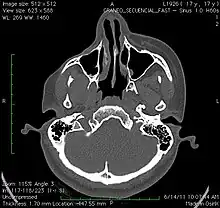

El diagnóstico se realiza basándose en los síntomas y la exploración. Se realizan pruebas complementarias como la resonancia magnética nuclear para comprobar el grado de afectación. Debe diferenciarse el mal de otras enfermedades que pueden dar síntomas parecidos, entre ellas la esclerodermia en golpe de sable, la hipoplasia facial congénita, la atrofia postradiación y la celulitis bacteriana.[1]